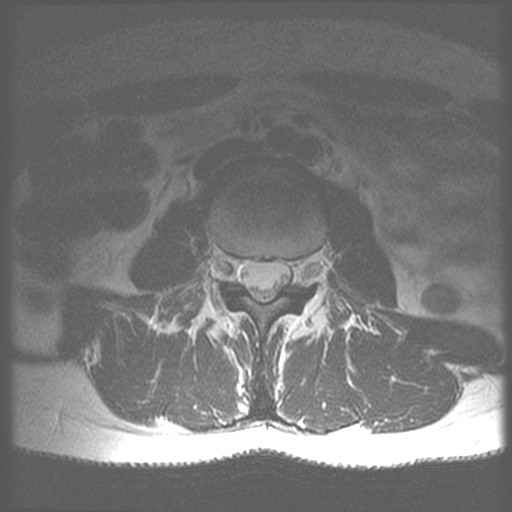

Lage Wervel Zuil